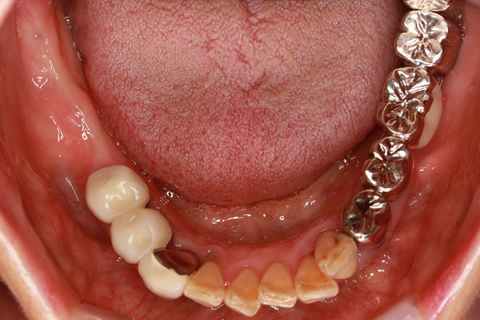

• 症例2

治療前

インプラント埋入時

治療後

年齢・性別

57歳男性

治療期間

3ヶ月

抜歯

なし

治療費

154万円

備考

左上5.6.7 及び左下6.7欠損

治療内容

左上5.6.7と左下6.7欠損部にインプラント埋入

施術の副作用(リスク)

オペによる知覚障害。インプラントによる歯肉炎。インプラント脱落。